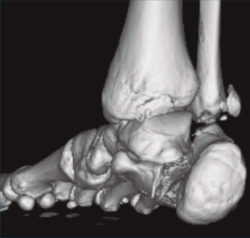

Se trata de un varón de 19 años que ingresa en reanimación tras precipitarse desde una altura de aproximadamente 10 metros. El paciente presenta una fractura estallido de L3 con afectación del canal medular junto con una fractura del vértice inferior de L4, así como una fractura luxación de calcáneo, asociada a una fractura del maléolo peroneo y del maléolo tibial posterior (Figuras 1 a 6) diagnosticadas mediante TC total body (por eso no se dispone de radiografías simples al momento del ingreso). Como podemos comprobar, se trata de una fractura de doble trazo de tipo hundimiento/depresión de la carilla articular (Figuras 5 y 6).

Figura 4. Luxación fragmento posterolateral.

Figura 5. Fractura maléolo peroneo, luxación astrágalo, fractura de doble trazo en calcáneo.

Figura 6. Fractura de doble trazo; se evidencia afectación de la articulación calcaneocuboidea.